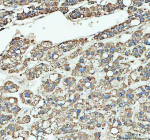

Immunohistochemical staining of ARHGEF12L using anti-ARHGEF12L antibody. ARHGEF12L was detected in a paraffin-embedded section of human parotid acinar cell carcinoma tissue. Heat mediated antigen retrieval was performed in EDTA buffer (pH 8.0, epitope retrieval solution). The tissue section was blocked with 10% goat serum. The tissue section was then incubated with 2 ug/ml rabbit anti-ARHGEF12L antibody overnight at 4oC. Peroxidase Conjugated Goat Anti-rabbit IgG was used as secondary antibody and incubated for 30 minutes at 37oC. The tissue section was developed using an HRP secondary and DAB substrate.